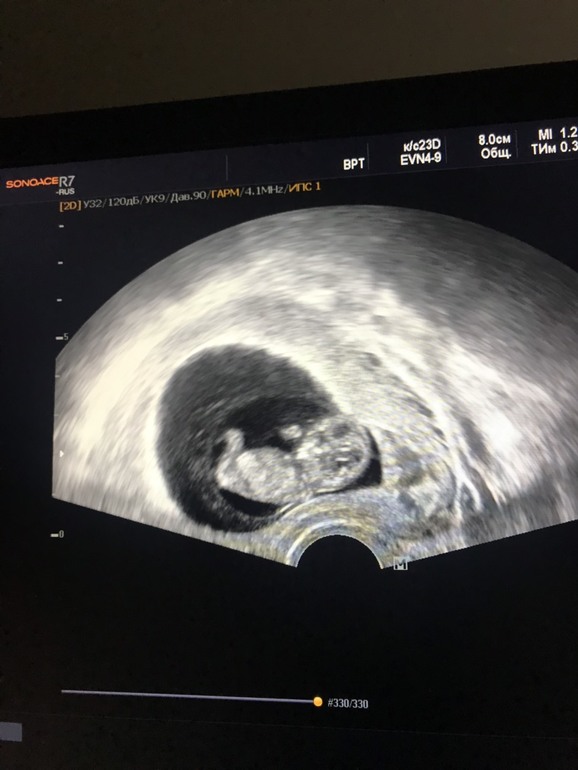

14.01 второе УЗИ и наш человечек

Человечку на фото 7недель и 4 дня

Единственное что сказал врач, что малыш крупненький. И я считала от дня переноса, а по развитию человечка сказали считать + 5 дней эмбриона , т.е. на фото 8недель и 2 дня.